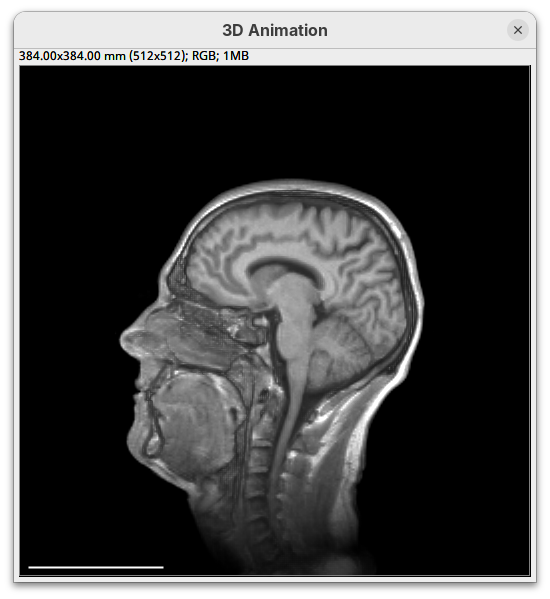

We will begin by visualizing an MRI dataset of a human head that is bundled in Fiji.

- Go to

File>Open Samples>T1 Head (16-bits).

- Increase the zoom to 200% for better visualization.

Orthogonal Views

Orthogonal Views is a tool that shows the optical sections through the orthogonal planes of XY: XZ and YZ. It is an easy and quick way to get a sense of the tridimensionality of your dataset. Whenever I’m opening a dataset for the first time I use Orthogonal Views. To activate it:

- Click on

Image>Stacks>Orthogonal Views(or pressCtrl+Shift+H). - The XZ and YZ panels will open next to your XY stack.

- The yellow lines are synchronized between the panels.

- Click around the different parts of the head to inspect the same position under different angles.

Orthogonal Views is a great way to start understanding your 3D data.

Volume Viewer

Volume Viewer is a more powerful plugin for 3D visualization as it supports slicing, projections, and rendering. The interface is interactive and intuitive to use. To open it:

- Go to

Plugins>Volume Viewer. The main interface will open in theSlicemode.

- Click around and move the sample to see optical sections from different angles.

- Then, activate the

Volumemode to render the sample’s surface in 3D and explore it as well, playing with the different rendering parameters.

Volume Viewer also provides a way to take snapshots of the current view.

BigDataViewer

BigDataViewer (Pietzsch et al. 2015) is one of the most important tools for visualizing large, multidimensional datasets. It provides a simple and intuitive interface and shortcuts to swiftly navigate through your sample even on a regular laptop. This is possible because of the underlying file format used by BigDataViewer: the XML/HDF5 combo. Therefore, before opening the plugin, we must convert our dataset.